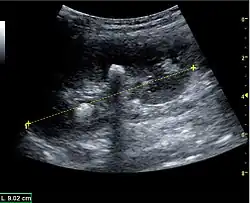

Masses are seen as a distortion of the normal renal architecture. Most renal masses are simple cortical renal cysts with a round appearance and a smooth thin capsule encompassing anechoic fluid. The incidence increases with age, as at least 50% of people above the age of 50 have a simple cyst in one of the kidneys. Cysts cause posterior enhancement as a consequence of reduced attenuation of the ultrasound within the cyst fluid (Figure 5). The simple cyst is a benign lesion, which does not require further evaluation.[1]

Figure 5. Simple renal cyst with posterior enhancement in an adult kidney. Measurement of kidney length on the US image is illustrated by '+' and a dashed line.[1]